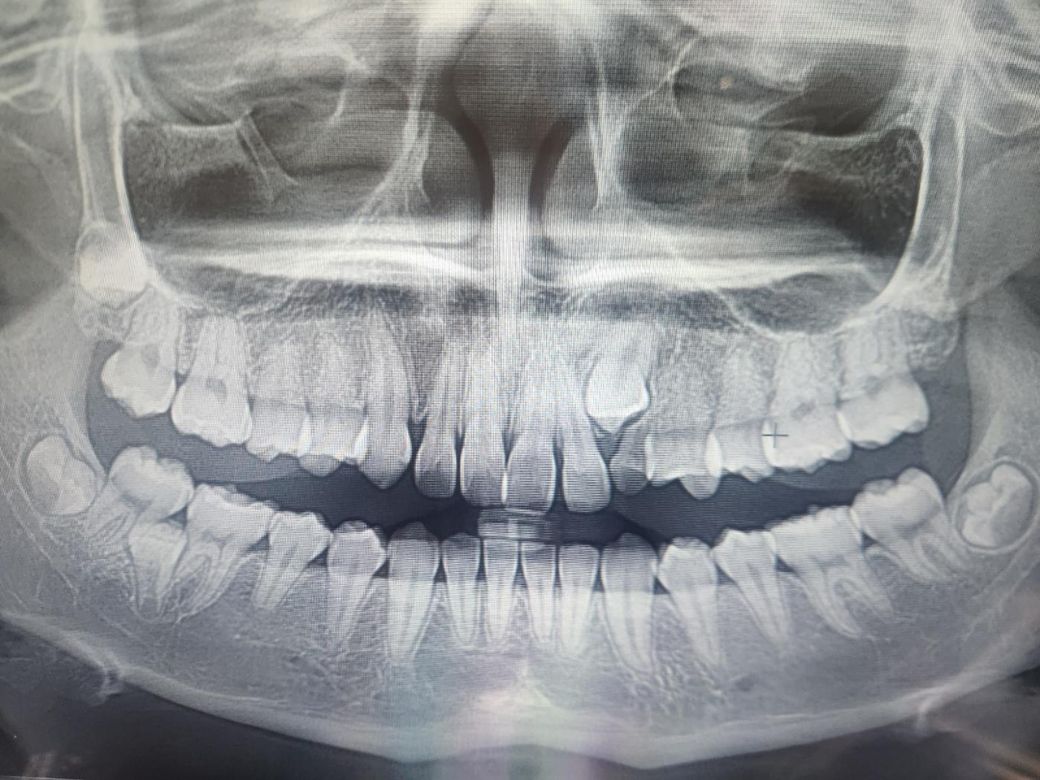

고등 여자 학생 엄마입니다. 사랑니는 안아픈데 어금니 앞쪽 과잉치가 어금니를 눌러서 아픈 상황이에요 사랑니까지 발치 진행하면 좋겠다고 하셔서요, 사랑니까지 같이 발치하게되면 너무 아프지 않을까 싶어서요 ㅠㅠㅠ왼쪽 어금니 쪽 입니다.

엑스레이는 좌우 반전입니다 엑스레이 사진상 말고 실제 방향으로 설명드립니다

오른쪽 아래 과잉치가 어금니 사이에 있고 이건 과잉치또는 미맹출한 유치일수도 있습니다 어쨌든 양 옆 어금니에 영향을 줄 수 있고 물혹을 형성할 수도 있으나 빼면서도 기존 어금니에 영향을 줄 수 있으므로 ct찍고 발치 여부 신중하게 고려해봐야 합니다 대학병원 상담 받아보세요

양쪽 아래 사랑니는 아직 만들어지는 중이고 맹출전이므로 꼭 당장 뺄 필요 없습니다

왼쪽 위 유치잔존, 송곳니 매복상태인데 유치빼주고 영구치 송곳니 내려올 수 있도록 견인교정해줘야 합니다